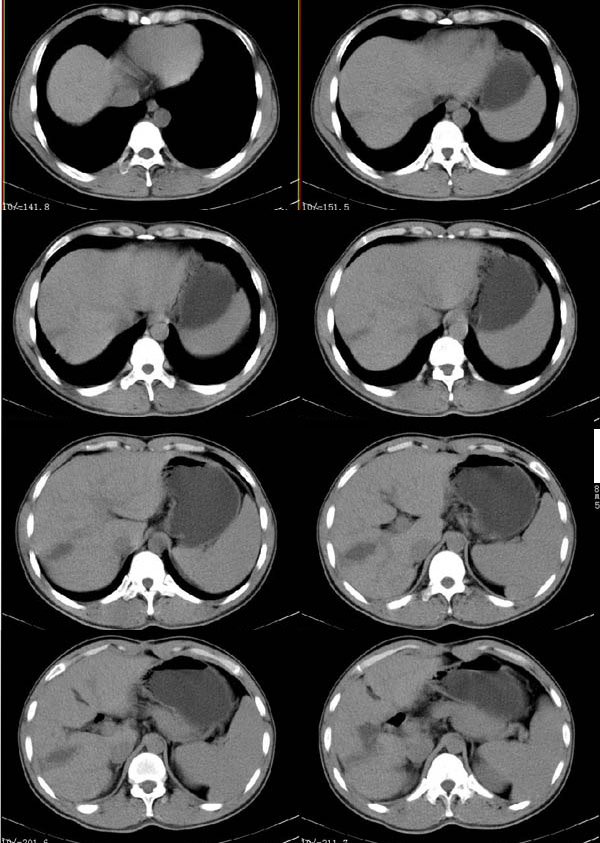

标题: CT4408:(续)肝癌术后CT表现

肝癌术后3个月(该患者硕士研究生,在四川开了一个宾馆.于做ct后第三天便在四军大西京医院做了手术,手术顺利.病人恢复良好.病理结果:肝细胞癌.最后诊断:原发性肝癌.)

10mm层厚扫描: